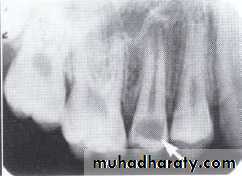

Dentin dysplasia, type I. panoramic & periapical films of the same case show the short and poorly developed roots, obliterated pulp chambers and root canals, and periapical inflammatory lesions.